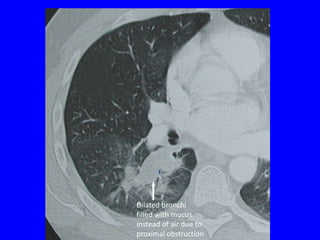

POST-OBSTRUCTIVE

• Dilated bronchi distal to obstruction filled

Dilated bronchi

filled with mucus

Branching

tubular opacity

instead of air due to

proximal obstruction